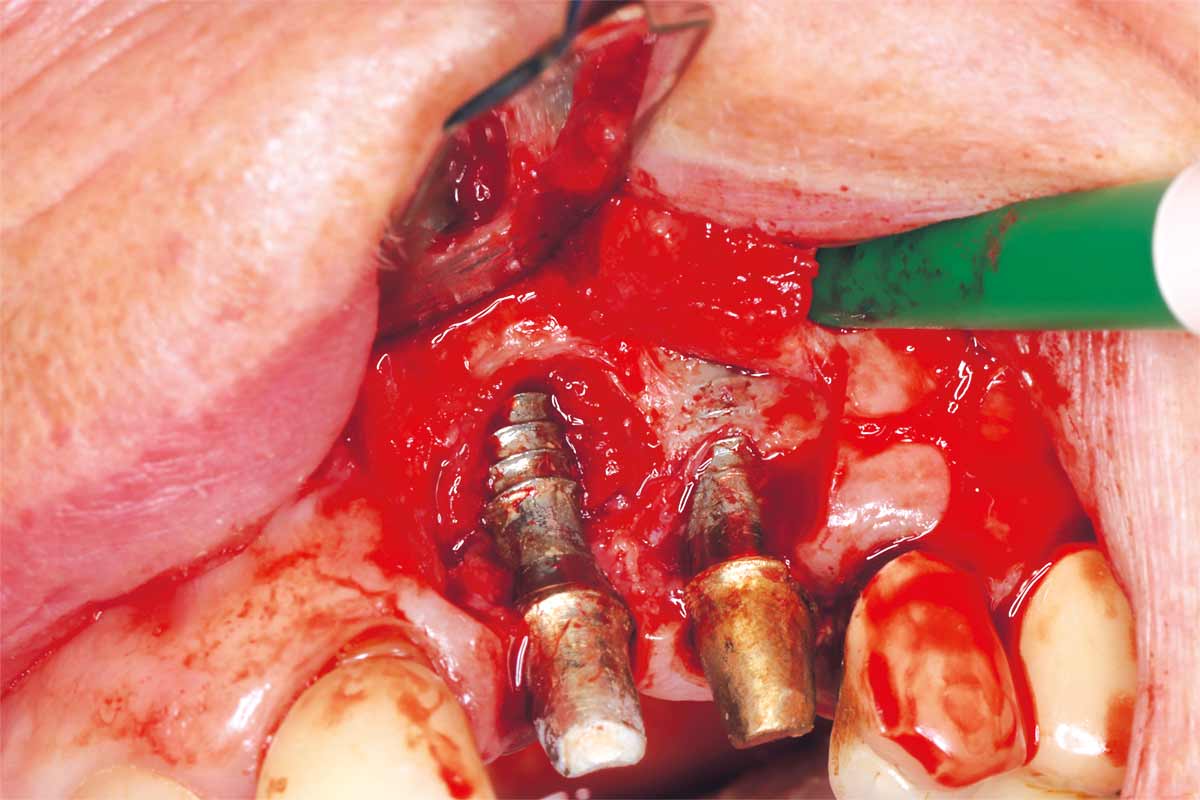

Ridge management following implant explantation - Dr. P.-Y. Gegout & Prof. Dr. O. Huck

Pre-operative: loss of interdental papilla between 12 and 11 associated with gingival inflammation and pus